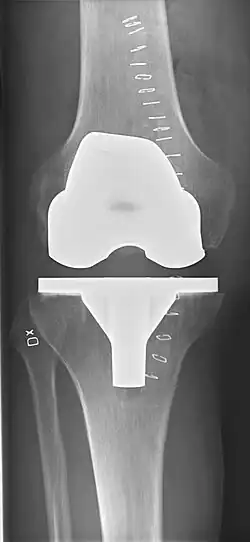

Knee replacement surgery can be performed as a partial or a total knee replacement.[3] In general, the surgery consists of replacing the diseased or damaged joint surfaces of the knee with metal and plastic components shaped to allow continued motion of the knee.

Femoral replacement

A round-ended implant is used for the femur, mimicking the natural shape of the joint. On the tibia the component is flat, although it sometimes has a stem that goes down inside the bone for further stability. A flattened or slightly dished high-density polyethylene surface is then inserted onto the tibial component so the weight is transferred metal to plastic, not metal to metal. During the operation any deformities must be corrected, and the ligaments balanced so the knee has a good range of movement, and is stable and aligned. In some cases the articular surface of the patella also is removed and replaced by a polyethylene button cemented to the posterior surface of the patella. In other cases, the patella is replaced unaltered.